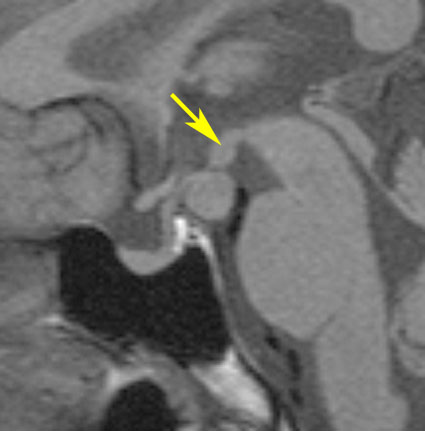

無症候で発見されたpedunculated typeです。視床下部の底面からぶら下がるようにしてあります。左のCISS画像で形がよくわかります。中央のT1では灰白質と等信号です。右のT2では高信号となっています。

乳頭体(矢印)からは離れているタイプです。ですから笑い発作を生じません。右側のガドリニウム増強画像ではまったく増強されていないのが特徴です。